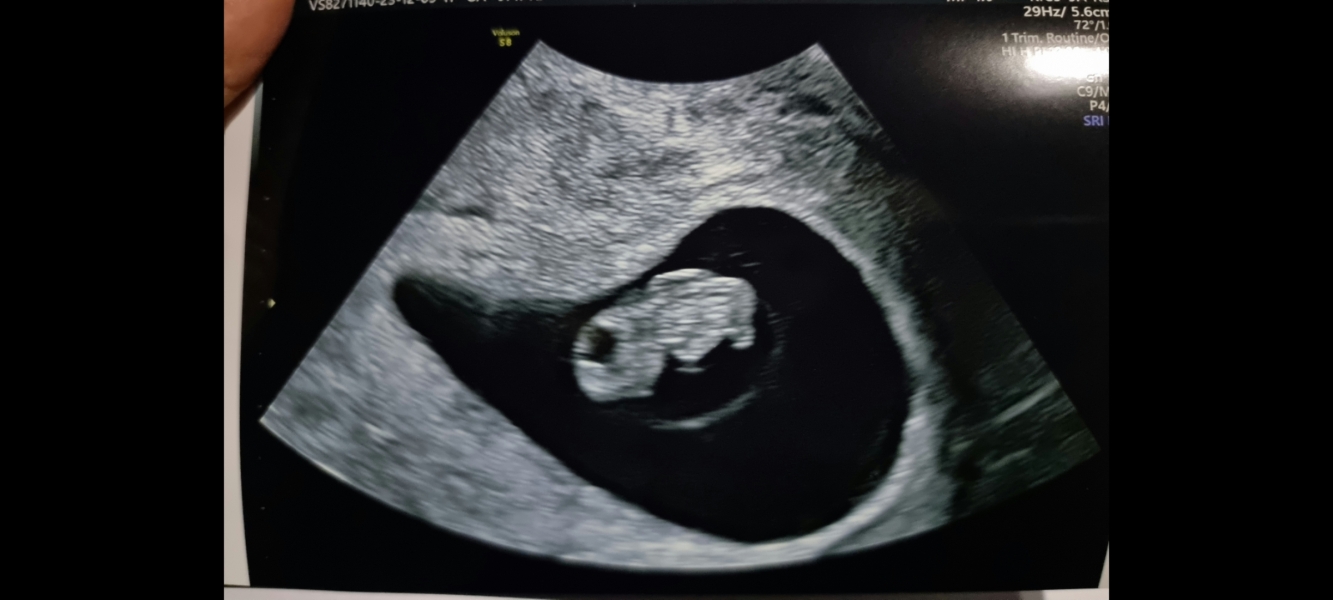

Hello ladies. Had our early private scan today. Saw one baby with a heartbeat. Thought I was 7 weeks 5 days but baby measure 8 weeks 3 days. So 5 days ahead.

@soon2be6 yes definitely planning to find out the gender. Already impatient to do so

@FigandHoney awww how lovely! Your scan is so clear!